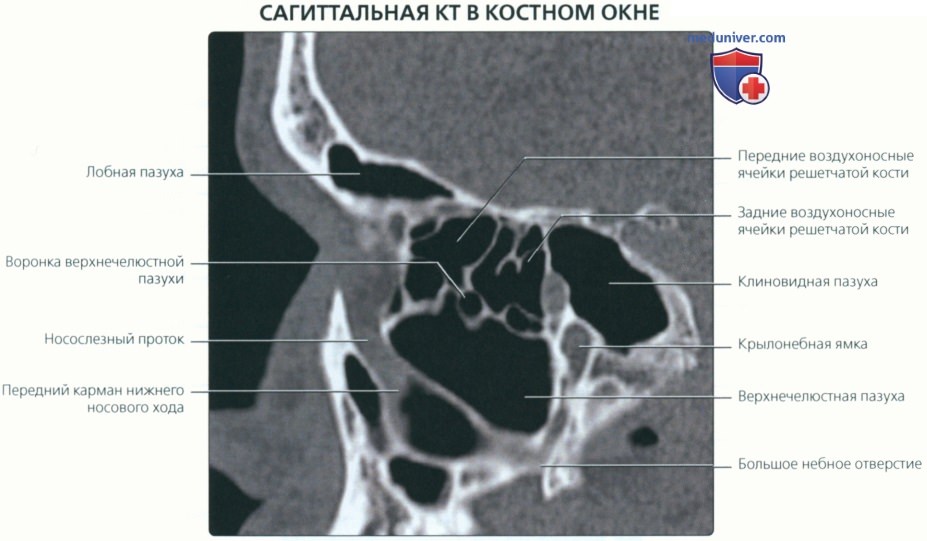

КТ анатомия сосцевидного отростка: особенности и показания